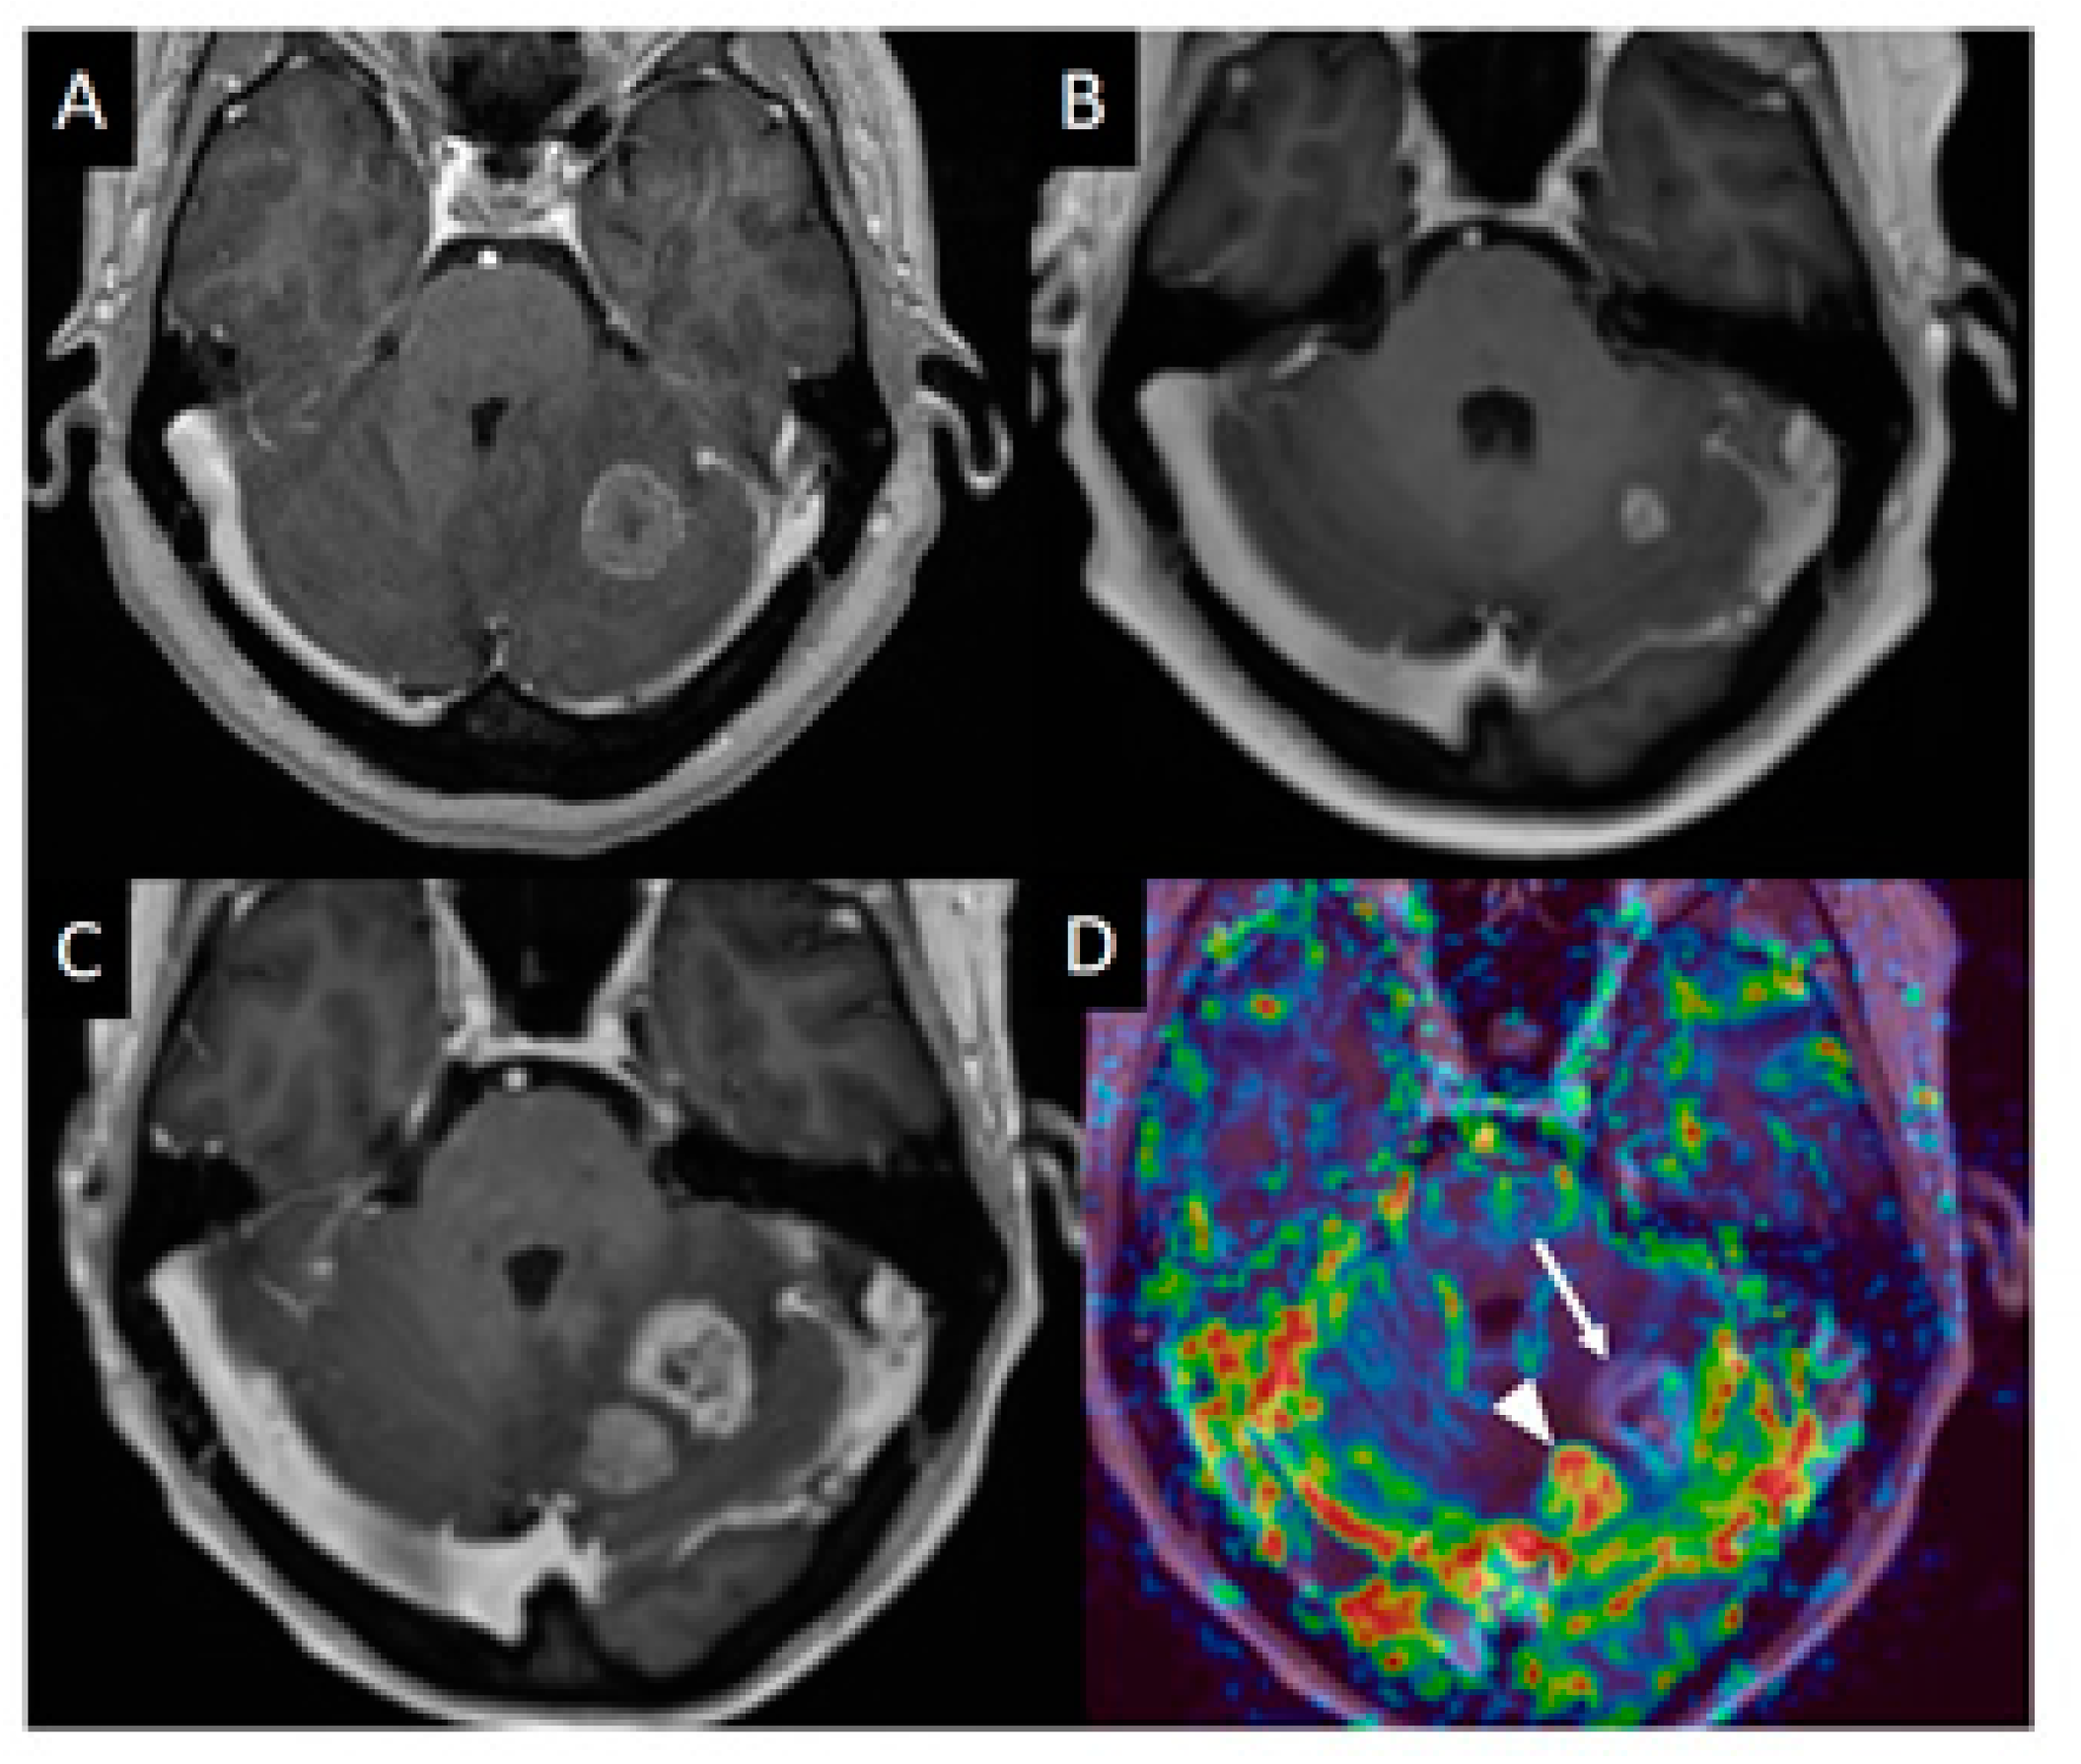

DSC is the most commonly used MR perfusion technique. It is acquired during the first pass of a compact gadolinium bolus through the brain vessels and generally employs an echo planar T2*-weighted gradient echo sequence with a temporal resolution of 1–2 s. Total acquisition time is usually less than 2 min. Gadolinium shortens the T2 and T2* of the tissue resulting in decreased signal along the vessels and tissues surrounding the vessels. Multiple parameters can be derived from this technique, with cerebral blood volume (CBV)—which reflects vessel density—being the most frequently used in brain tumors (see Figure 1). DSC does not provide absolute CBV values, therefore values are often expressed as relative metrics compared to normal appearing white matter or grey matter (rCBV). A new DSC technique consisting in the simultaneous acquisition of gradient echo and spin echo DSC perfusion shows great promise [19]. This technique provides, not only an estimation of vessel density but also an estimation of mean vessel size and vessel type (arterial or venous dominance).

DSC perfusion is used in clinical practice for characterization of brain masses, glioma grading, and, most commonly, for the differentiation between treatment-related abnormalities mimicking tumor progression and true recurrent tumor. Many studies have investigated the use of DSC derived CBV for differentiation between treatment related changes and true tumor progression in gliomas and brain metastasis [20,21,22,23]. The two most common approaches to measure CBV are mean lesion value and maximum lesion value (“hot spot” approach). A recent meta-analysis showed pooled sensitivities and specificities for detecting tumor recurrence in high-grade gliomas using the mean rCBV (threshold range, 0.9–2.15) and maximum rCBV (threshold range, 1.49–3.1) corresponding to 88% and 88% (95% CI: 0.81–0.94; 0.78–0.95) and 93% and 76% (95% CI: 0.86–0.98; 0.66–0.85), respectively [20]. In a head-to-head comparison between DCE and DSC for the differentiation between tumor recurrence and radiation necrosis in treated high grade gliomas, DSC perfusion showed higher diagnostic accuracy than DCE perfusion [24].